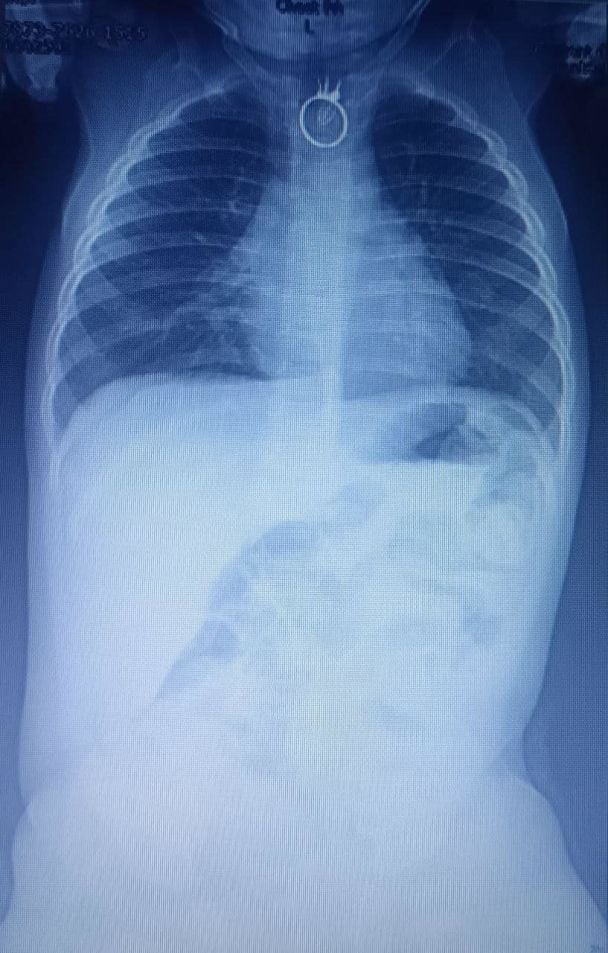

"Тоді вони зрозуміли, що, можливо, хлопчик проковтнув сторонній предмет. Після цього батьки одразу вирушили до місцевої лікарні в Новому Роздолі. Там лікарі провели малюкові рентген, на якому виявили стороннє тіло. Згодом дитину негайно каретою швидкої допомоги доправили до Центру дитячої медицини лікарні "Охматдит", - йдеться у повідомленні.

"Одразу після госпіталізації, о другій годині ночі, ми взяли дитину на операційний стіл і провели ригідну езофагоскопію з видаленням стороннього тіла. Це був перстень. Все минуло успішно та без особливостей. Однак іграшковий перстень трохи пошкодив стравохід", – розповів дитячий хірург Олександр Колодій.